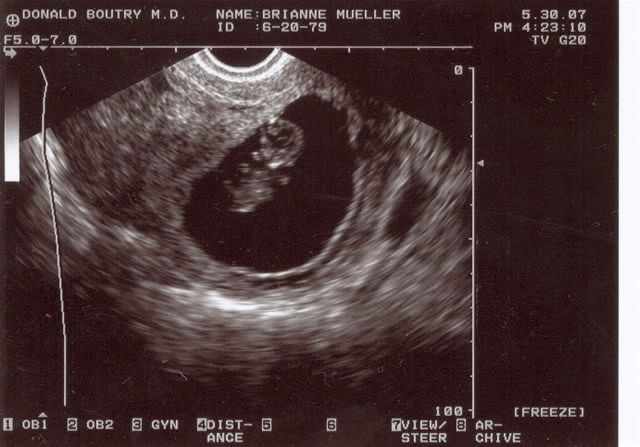

Isabella's Ultrasound Pics